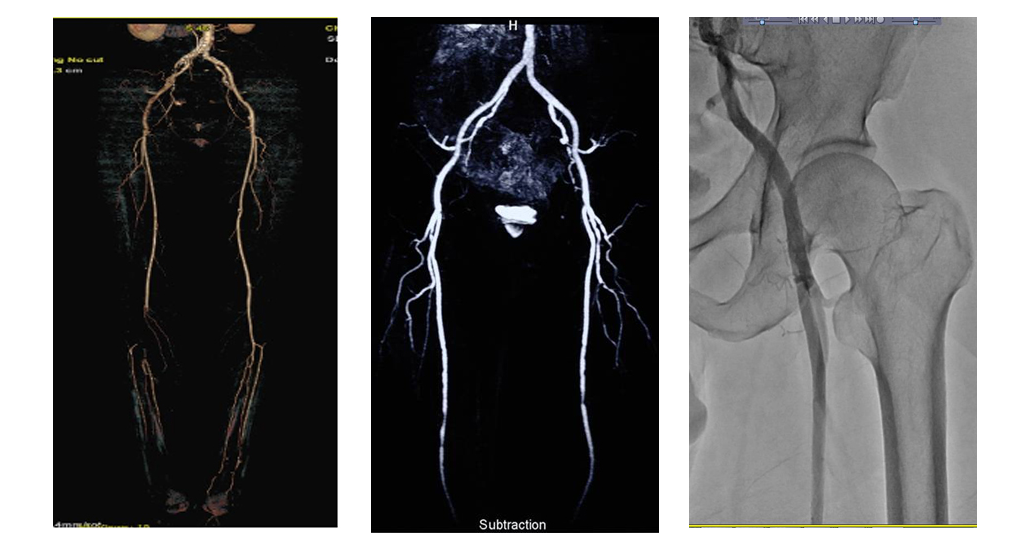

- 경피적 혈관 성형술 (Percutaneous Transluminal Angioplasty, PTA):

- 혈관의 좁아진 부분을 확장하는 시술로, 풍선을 이용해 혈관을 넓히고, 좁아진 부위를 확장하여 혈류를 개선합니다.

- 이 방법은 주로 좁아진 동맥에 풍선을 삽입하여, 동맥을 확장하고 정상적인 혈류를 회복시키는 데 사용됩니다.

- 스텐트 삽입술 (Stent Placement):

- 스텐트는 혈관을 확장한 후, 혈관을 지지하는 금속 튜브입니다. 스텐트는 혈관이 다시 좁아지지 않도록 도와주며, 혈류를 유지하는 데 중요합니다.

- 스텐트 삽입술은 혈관 성형술 후에 혈관을 안정시키고, 혈관이 다시 좁아지는 것을 방지하는 데 사용됩니다.